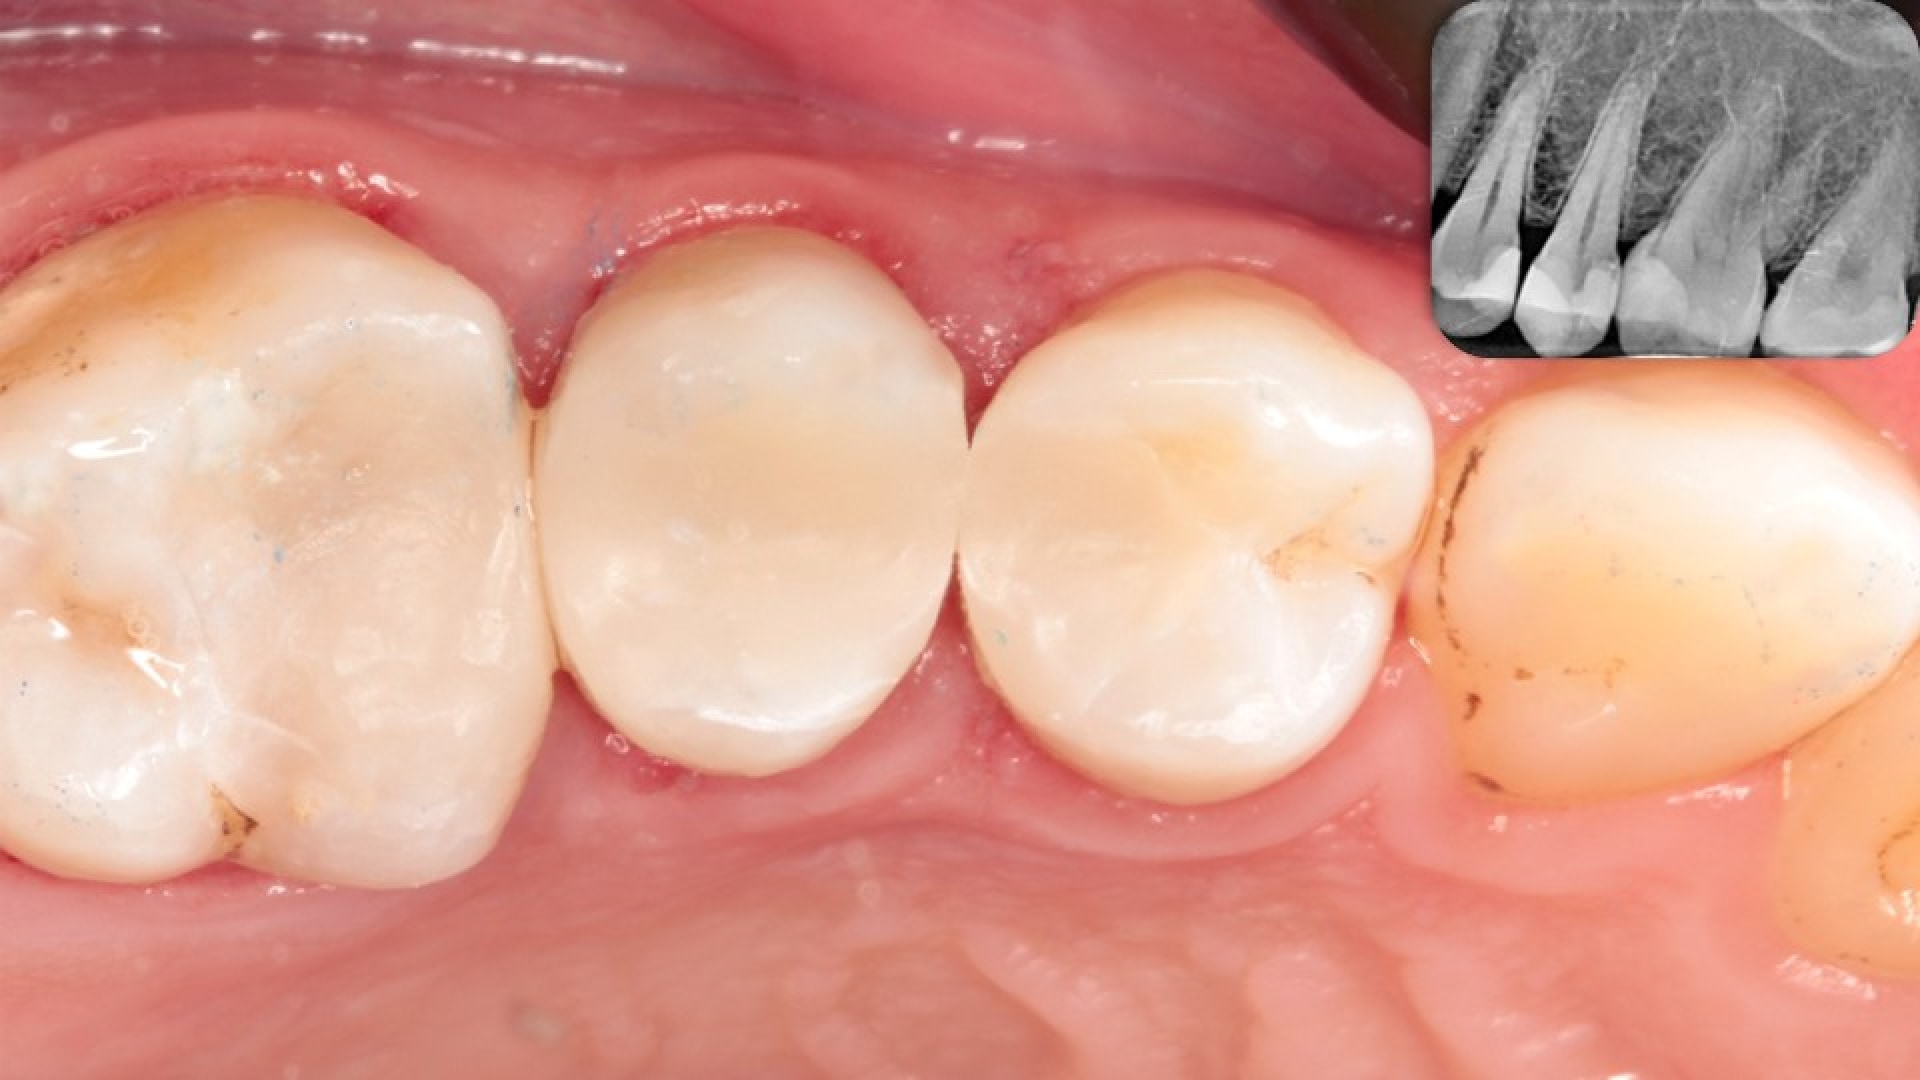

Stage 8. In with the new.

Further finishing & polishing was done to ensure proper margins, surface smoothness, contacts and occlusion. Patient was extremely satisfied with the results and after two weeks follow up, the original symptoms were resolved.